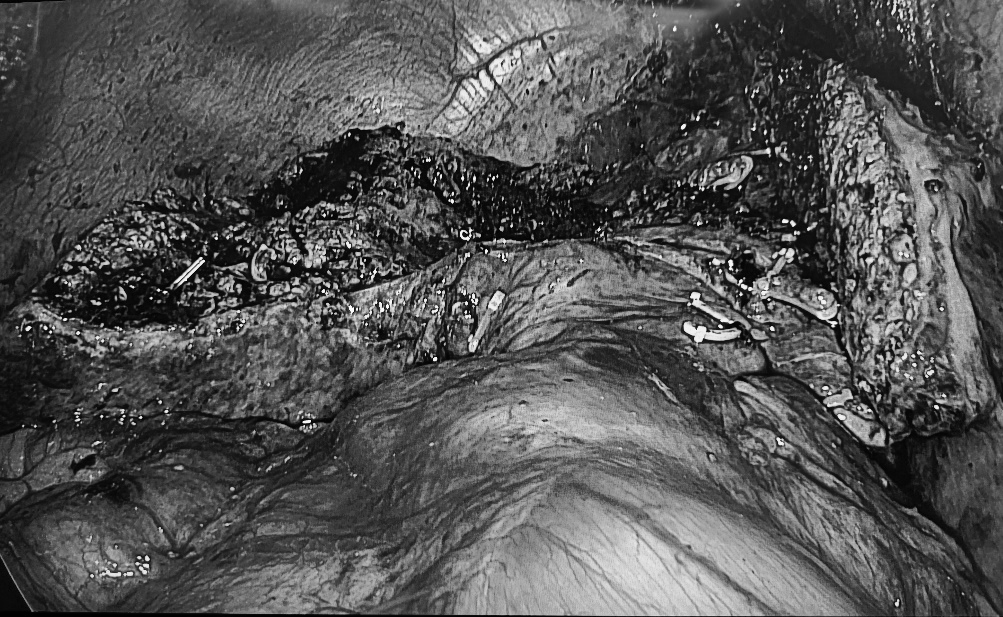

由科室副主任郭威主刀,科室副主任吴嘉兴、住院医师李伟锋组成的手术团队采用经腹腔镜荧光反染引导肝中叶(Ⅳ+Ⅴ+Ⅷ段)切除术,术后患者恢复顺利,痊愈出院。

本病例手术成功,标志着医院肝胆胰外科对复杂肝癌的治疗将迎来更加「微创化和精准化」的发展阶段,实现最大的治疗效果和最小的手术创伤。今后,科室也将继续不断开拓创新,持续学习和引进国内外先进技术,培养高素质人才梯队,打造地区优势专科,为患者提供更优质、高效、精准的医疗服务。